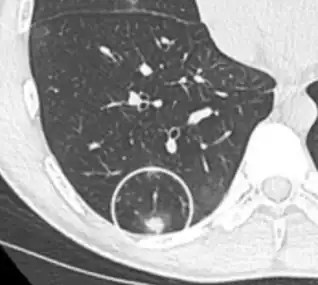

CT scan

For incidentally detected nodules on CT scan, Fleischner Society guidelines are given in table below. For multiple nodes, management is based on the most suspicious node.[8] These guidelines do not apply in lung cancer screening, in patients with immunosuppression, or in patients with known primary cancer.[8]